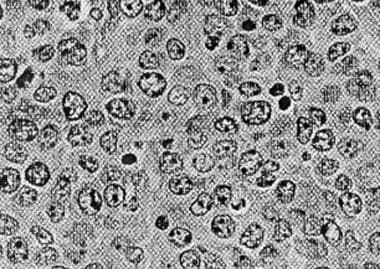

Reflecting on a patient experience during a fellowship in 2015, Suchitra Sundaram, MD, notes how the standard treatment for stage IV ABC-subtype diffuse large B-cell lymphoma (DLBCL) was R-CHOP chemotherapy, which cured around 60% of patients. Advances in lymphoma biology since that time have led to better risk assessment and identification of high-risk patients, prompting new clinical trials.

One such trial, POLARIX, combined R-CHOP with the antibody-drug conjugate polatuzumab vedotin, showing a 27% reduction in disease progression risk. This combination has been approved for first-line treatment and offers particular benefits for older patients with ABC-subtype DLBCL and high International Prognostic Index scores, with ongoing trials exploring new drug combinations.